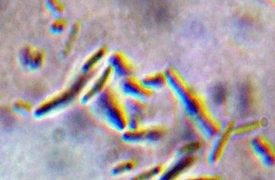

関節炎は、感染性関節炎や新生子牛多発性関節炎とも呼ばれ、子牛では生命を脅かす緊急事態と考えられ、迅速かつ積極的な治療が必要です。これは、関節の重篤な感染症です(一般的な部位は、飛節、膝関節、手根骨、まれに股関節や肩)。大腸菌、サルモネラ菌、...

子牛ジフテリアは、世界中の若齢子牛(5週齢~24ヶ月齢)に発生する壊死性喉頭炎であり、フソバクテリウム・ネクロフォーラム(Fusobacterium necrophorum)細菌による喉頭組織の感染によって引き起こされます。この疾患は急性ま...